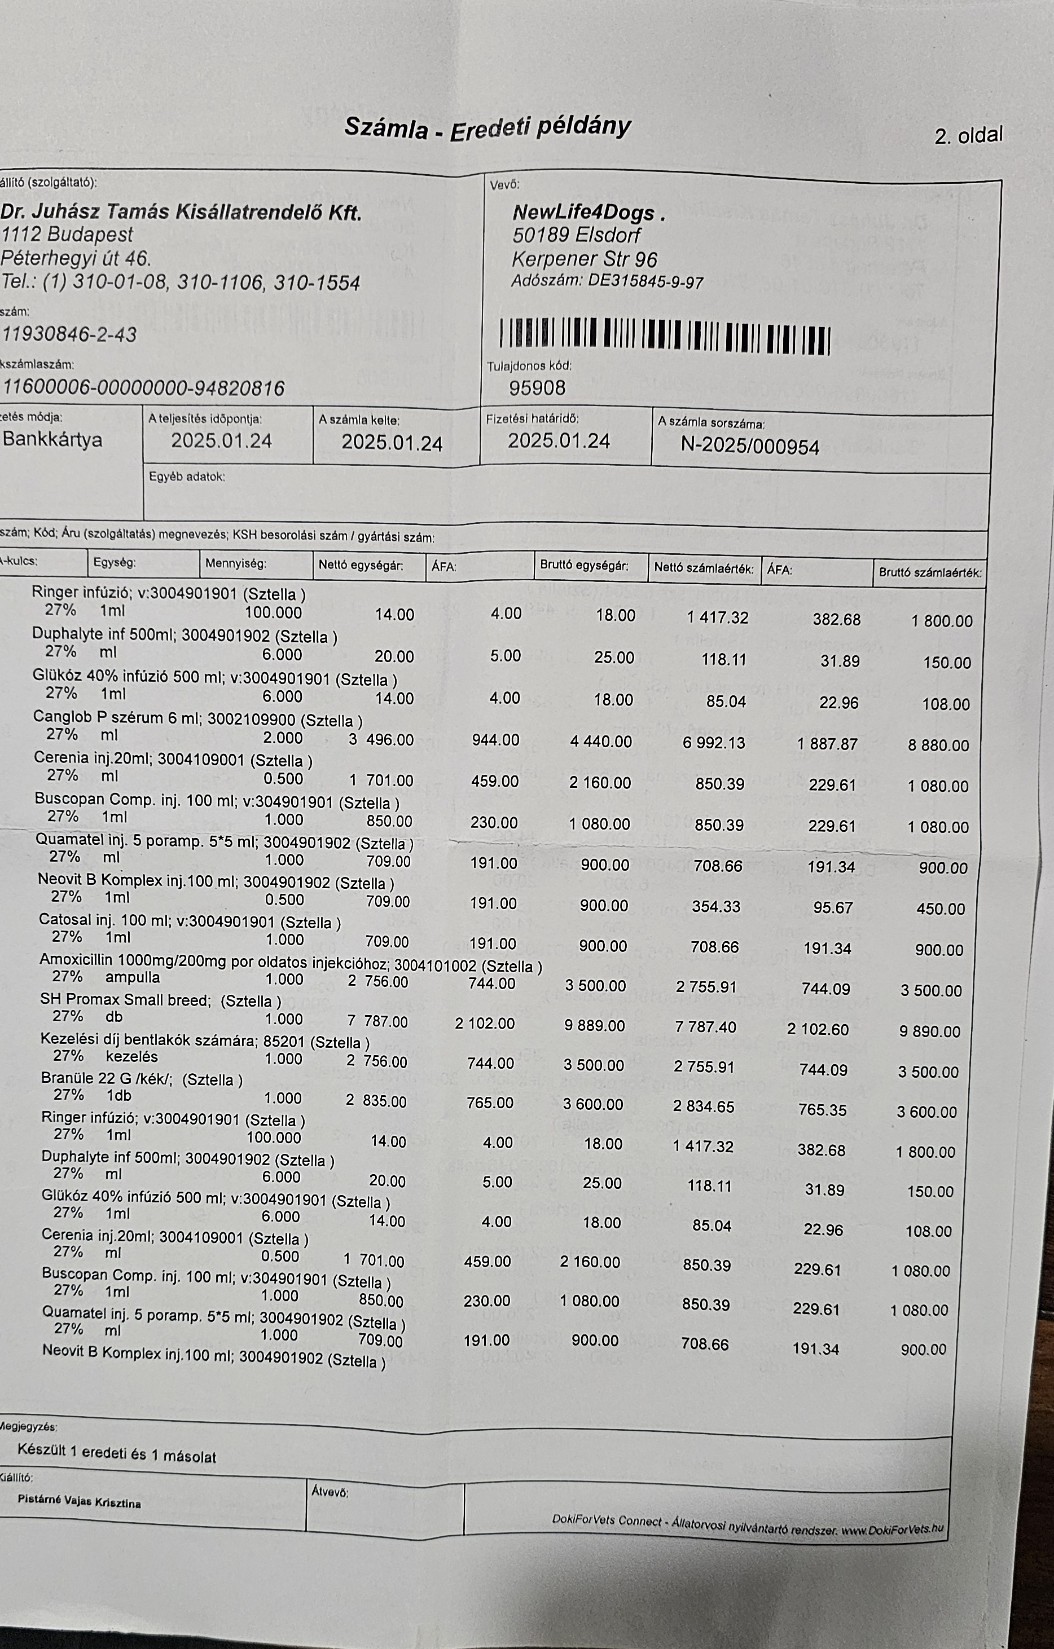

So zum Beispiel unsere kleine Stella, ein Welpen Mädchen das hier im Wald aufgefunden wurde. Nur 4 Tage nach Ankunft ging es Stella extrem schlecht und wir brachten sie in die Tierklinik zur stationären Aufnahme. Dort wurde sie intensivst medizinisch behandelt und musste 9 Tage in der Klinik verbleiben. Nur dieser eine Klinikaufenthalt verursachte Kosten in Höhe von 261.000,00 Forint ( ca. 640,00 Euro). Medikamente für die weitere Versorgung unserer Hunde musste bestellt werden. Ebenso Welpenfutter mussten wir nachkaufen. In den ersten Wochen wurden einige Hunde vergesellschaftet, damit die Quarantänestation wieder freie Zwinger hat. Denn in der Tötung warten Hunde darauf von uns abgeholt zu werden. Dies wird nun in den nächsten Tagen geschehen. Auch Klinikbesuche Kastrationen wurden wieder durchgeführt. Alleine hierfür betrug der finanzielle Aufwand ca. 750.000,00 (= ca. 1840,00 Euro) in der ersten Hälfte des Monats. Leider ist zur Zeit die Zeit extrem knapp, weswegen wir uns für die verspäteten Berichte entschuldigen. Doch die Rettungsaktionen und das Wohl unserer Schützlinge haben nun einmal Vorrang.

Nachdem die kleine Stella nach mehr als einer Woche die Klinik verlassen durfte, Mussten erneut einige unserer Neuzugänge dringende Not-OP´s und stationäre Aufnahme +ber sich ergehen lassen. So auch der kleine Sidney, den wir schwer verletzt mit gebrochenem Hinterbeinchen auf der Strasse in Nordungarn fanden. Sofortige Untersuchungen, Rüntgenaufnahmen und unverz+gliche Notoperation war erforderlich. Die Operation hat der kleine Mann gut überstanden. Nun benütigt er weitere Medikamente und Vitaminprodukte, damit er einen guten Heilungsprozess durchlaufen kann. Ebenso benütigt er 6 Wochen Zwingerruhe und Physiotherapie.